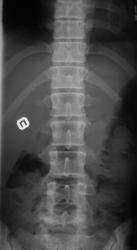

Пол пациента: Женский пол Тип патологии: Врожденная патология Область исследования: Скелетно-мышечная система Методы исследования: Rg Молодая женщина пришла на снимок поясничного отдела. Другая женщина, которая занимается рукопашным боем, обратилась с жалобами на боли в пояснице, после неудачного броска. https://radiomed.ru/sites/default/files/styles/case_slider_image/public/user/712/sl274202.jpg?itok=nrVgJub5 https://radiomed.ru/sites/default/files/styles/case_slider_image/public/user/712/sl274211.jpg?itok=ON6uvgKI https://radiomed.ru/sites/default/files/styles/case_slider_image/public/user/712/sl274212.jpg?itok=NmuMvaE1 https://radiomed.ru/sites/default/files/styles/case_slider_image/public/user/712/sl274213.jpg?itok=nP2dg6tE ID:18475 Пт, 27/01/2012 - 18:10 #1 Фаина Не на сайте Был на сайте: 2 года 11 месяцев назад Зарегистрирован: 14.12.2008 - 16:51 Публикации: 323 В первом случае, кроме остеохондроза и несросшихся апофизов, честно говоря, ничего критичного" не увидела. А во втором случае, не спондилолиз ли в L5?! Пт, 27/01/2012 - 18:17 #2 Наталия Не на сайте Был на сайте: 8 лет 7 месяцев назад Зарегистрирован: 30.07.2008 - 13:24 Публикации: 538 Во втором случае вероятнее спондилолиз. Пт, 27/01/2012 - 18:25 #3 Глазков Игорь А... Не на сайте Был на сайте: 9 месяцев 1 неделя назад Зарегистрирован: 19.12.2008 - 20:41 Публикации: 1597 Шморля в каудальной части тела позвонкаТ12 Прийди к Себе Пт, 27/01/2012 - 21:15 #4 И.Бондаренко Не на сайте Был на сайте: 3 дня 7 часов назад Зарегистрирован: 13.09.2011 - 22:55 Публикации: 9206 Случай №1. Грыжа Шморля Т12, несросшиеся апофизы L2,5 или обызвествившиеся грыжи дисков. Случай №2. Спондилолиз дужки L5. Ср, 01/02/2012 - 21:08 #5 Natalja Не на сайте Был на сайте: 13 лет 10 месяцев назад Зарегистрирован: 27.01.2012 - 22:08 Публикации: 4 Глазков Игорь Артурович wrote: Молодая женщина пришла на снимок поясничного отдела. Другая женщина, которая занимается рукопашным боем, обратилась с жалобами на боли в пояснице, после неудачного броска. В первом случае смущает L2, травмы не было? Чт, 02/02/2012 - 14:35 #6 Глазков Игорь А... Не на сайте Был на сайте: 9 месяцев 1 неделя назад Зарегистрирован: 19.12.2008 - 20:41 Публикации: 1597 травму отрицает Прийди к Себе

Случай №1. Грыжа Шморля Т12, несросшиеся апофизы L2,5 или обызвествившиеся грыжи дисков.

Случай №2. Спондилолиз дужки L5.